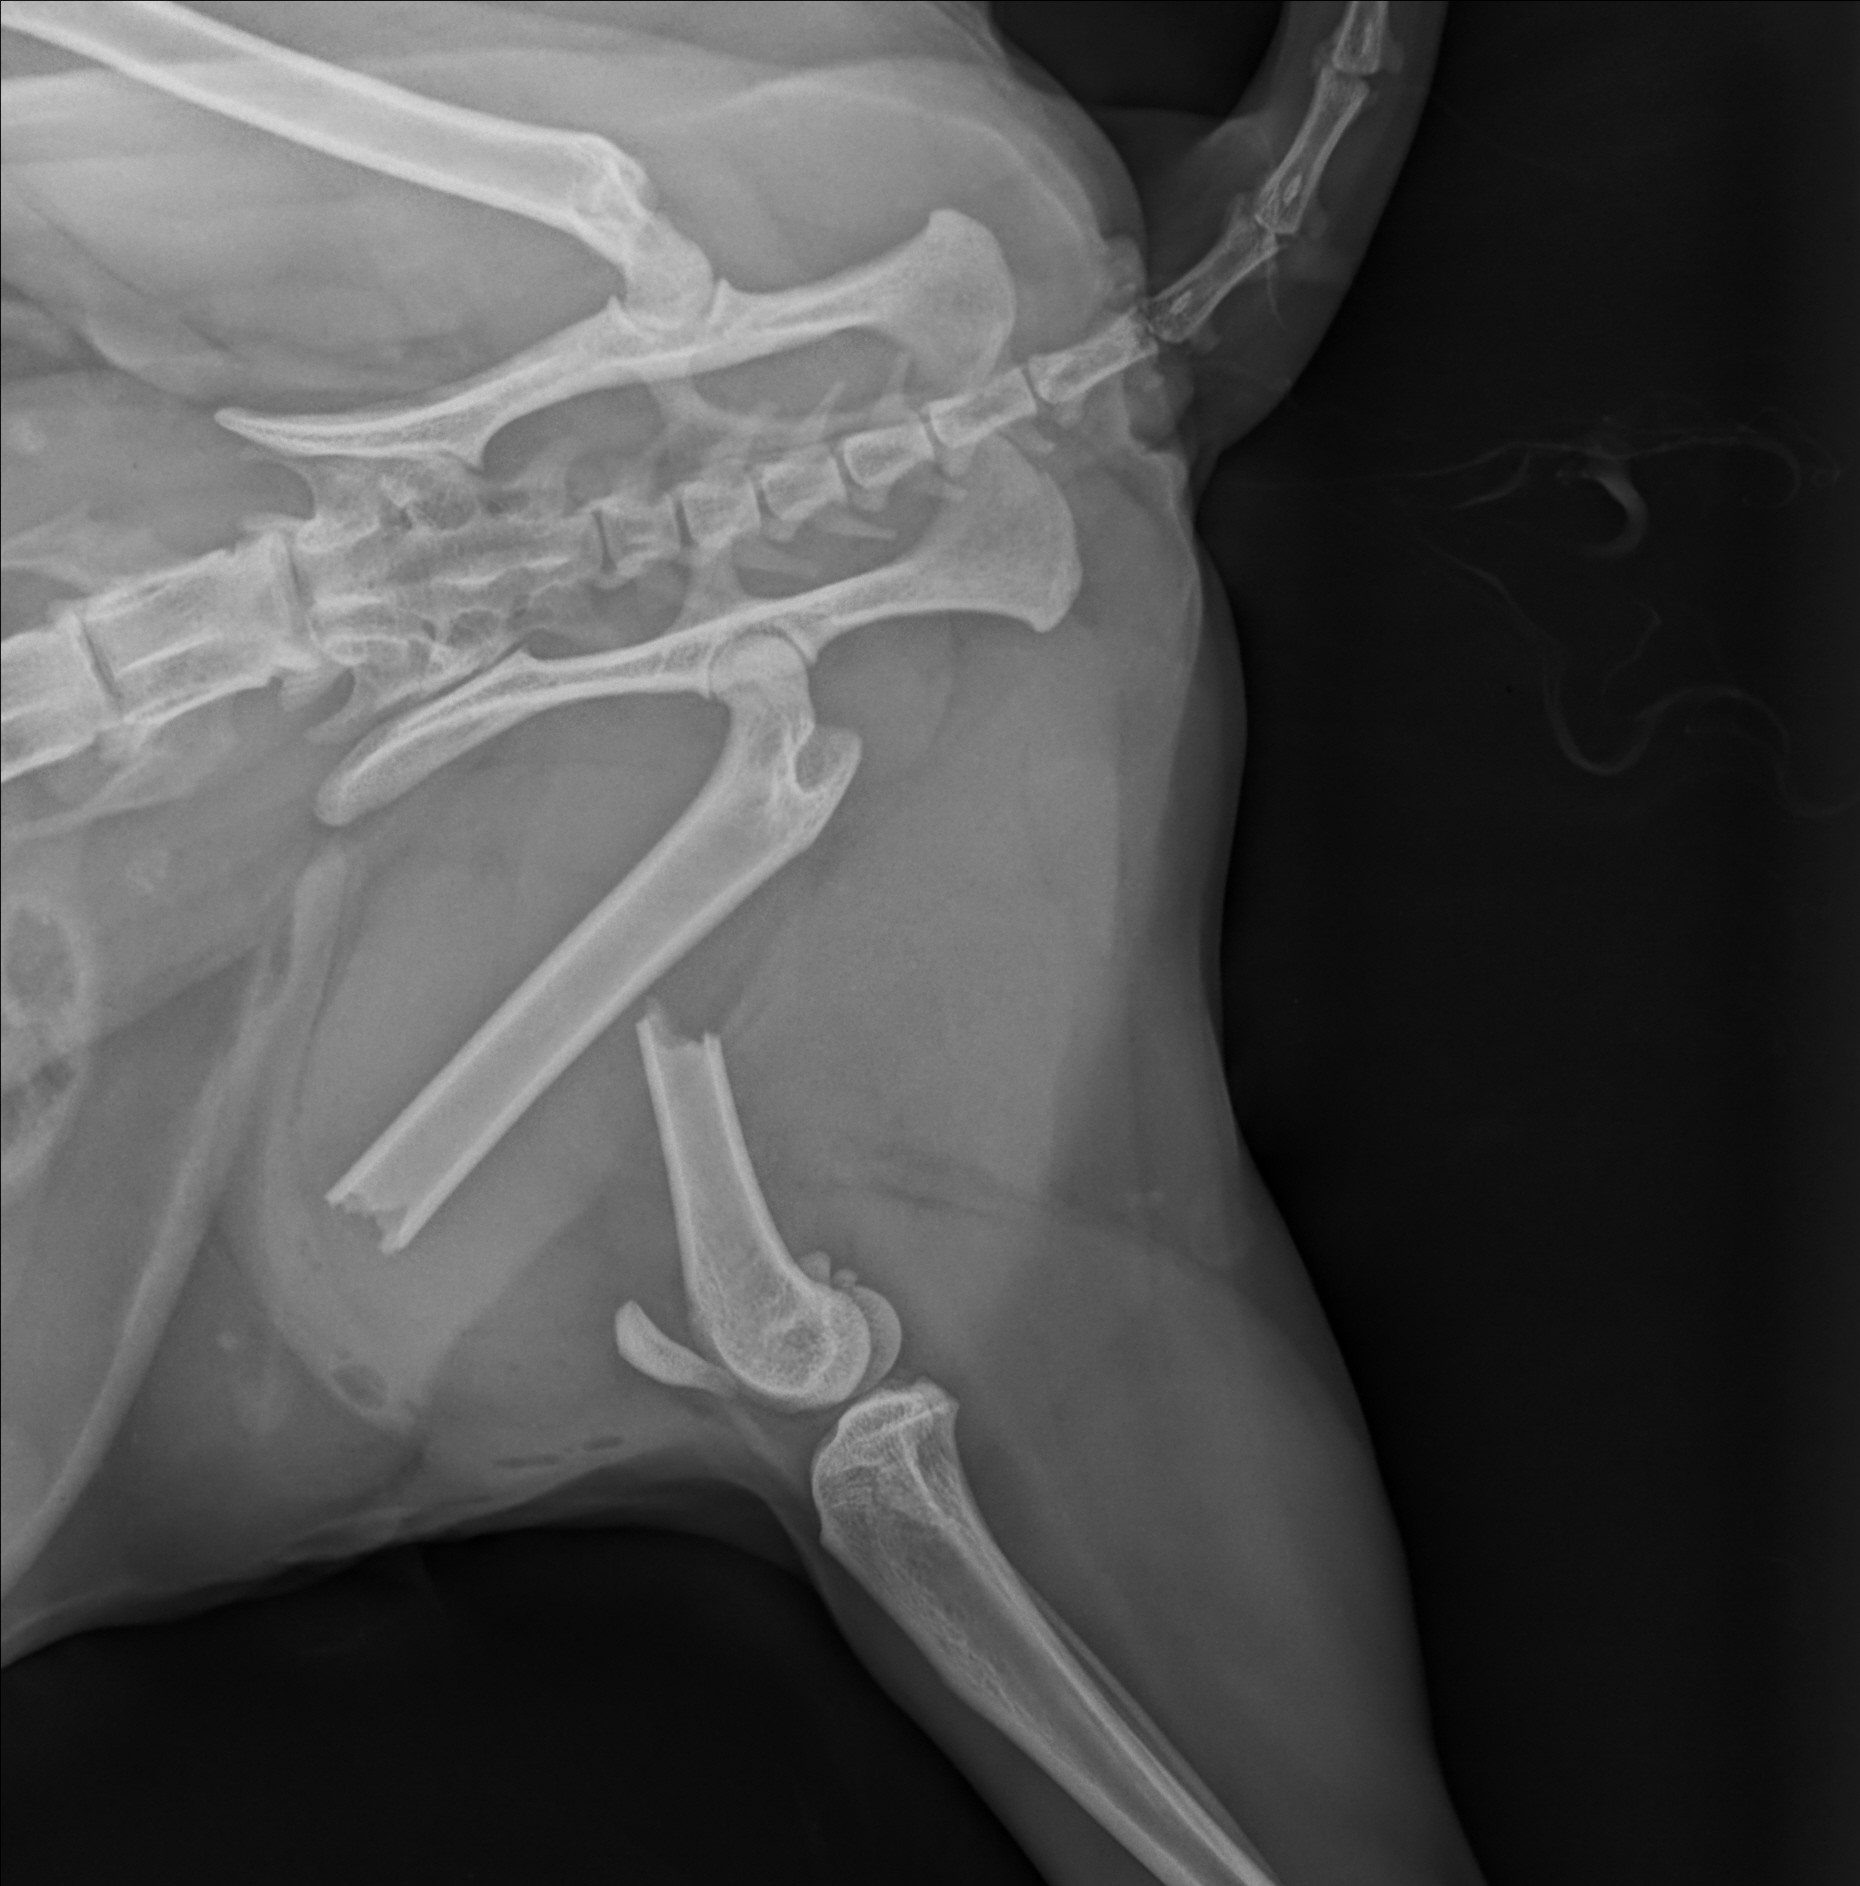

Mit modernstem digitalem Röntgen ermöglichen wir eine schnelle und detaillierte Diagnose – bei minimaler Strahlenbelastung und maximaler Aussagekraft. Ob Knochen, innere Organe oder Gelenke: Die hochauflösenden Bilder liefern in Sekundenschnelle klare Ergebnisse und bilden die Grundlage für eine gezielte, individuelle Behandlung.